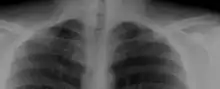

Most cases of cervical ribs are not clinically relevant and do not have symptoms;[7][8] cervical ribs are generally discovered incidentally, most often during x-rays and CT scans.[3][4][6] However, they vary widely in size and shape,[3] and in rare cases, they may cause problems such as contributing to thoracic outlet syndrome,[7] because of pressure on the nerves that may be caused by the presence of the rib.[7][9]

On imaging, cervical ribs can be distinguished because their transverse processes are directed inferolaterally, whereas those of the adjacent thoracic spine are directed anterolaterally.[11]